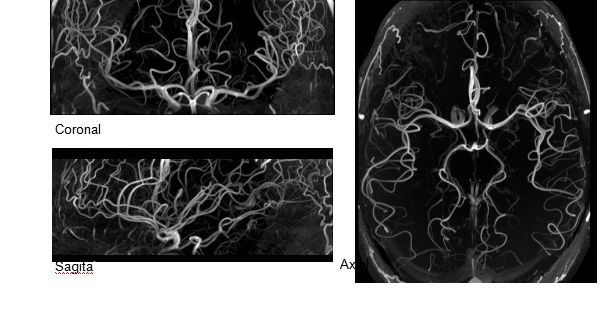

MAGNETOM Terra在業(yè)界首次實(shí)現(xiàn)了兩倍于傳統(tǒng)7T的超強(qiáng)梯度性能,實(shí)現(xiàn)超快速、超高效、超高分辨功能磁共振成像。如此高性能的梯度系統(tǒng)無論對于科研還是臨床都帶來了更多可能。

1毫米的各向同性分辨率DTI:神經(jīng)纖維束的交叉細(xì)節(jié)顯示

0.8毫米的各向同性分辨率:精確劃分灰質(zhì)和白質(zhì)

0.8毫米的各向同性分辨率:超精細(xì)的解剖細(xì)節(jié),例:小腦的精細(xì)結(jié)構(gòu)

超精細(xì)的解剖細(xì)節(jié):T2對比

0.17 x 0.17 x 0.8毫米分辨率超高。

(TOF)300微米的各向同性分辨率顯示最小的血管